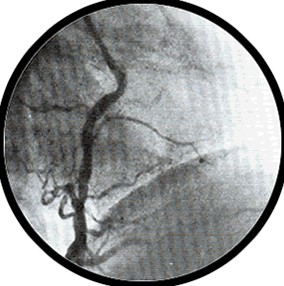

右前斜位:右冠状动脉 |

右冠状动脉象字母 “L” 1、右冠状动脉 2、右心室支 3、后降支

右冠状动脉象字母 “C” 1、右冠状动脉 2、右心室支 3、后降支 4、后侧支 |